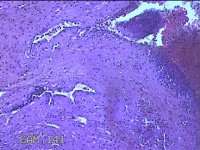

右侧卵巢囊肿

性别

女

年龄

临床诊断

一般病史

下腹痛3天。

标本名称

大体所见

灰白暗红色囊壁样组织2.5x1.5x0.3cm一块,表面糜烂,因已切开,囊内容物已流失,囊壁厚0.1cm。

图4